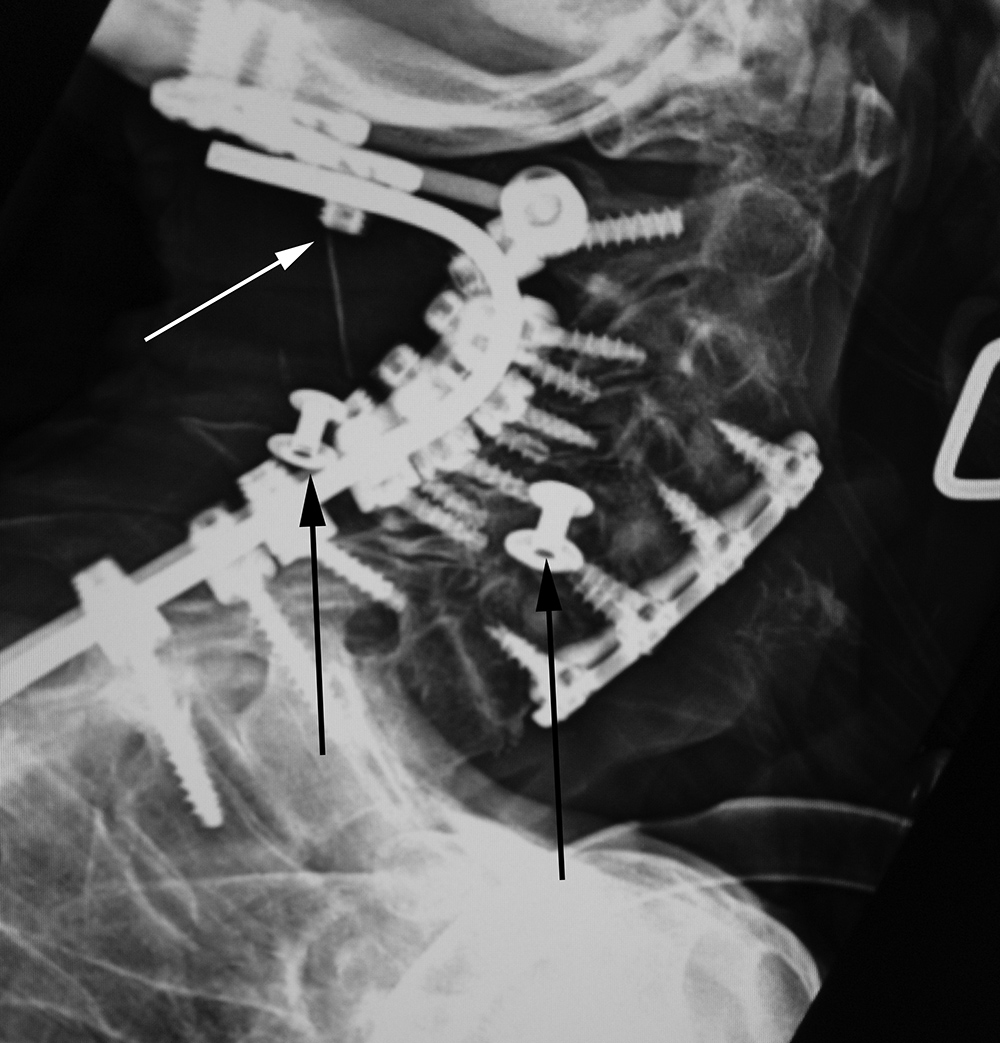

| 70 year-old woman with severe rheumatoid arthritis and chronic atlantoaxial subluxation. There is occiput to T1 posterior spinal fusion and anterior spinal fusion from C3 to C7. One of the occipital screws is "proud" (white arrow). Two gown snaps (black arrows) simulate dislodged apparatus. A tracheostomy tube is also present. |